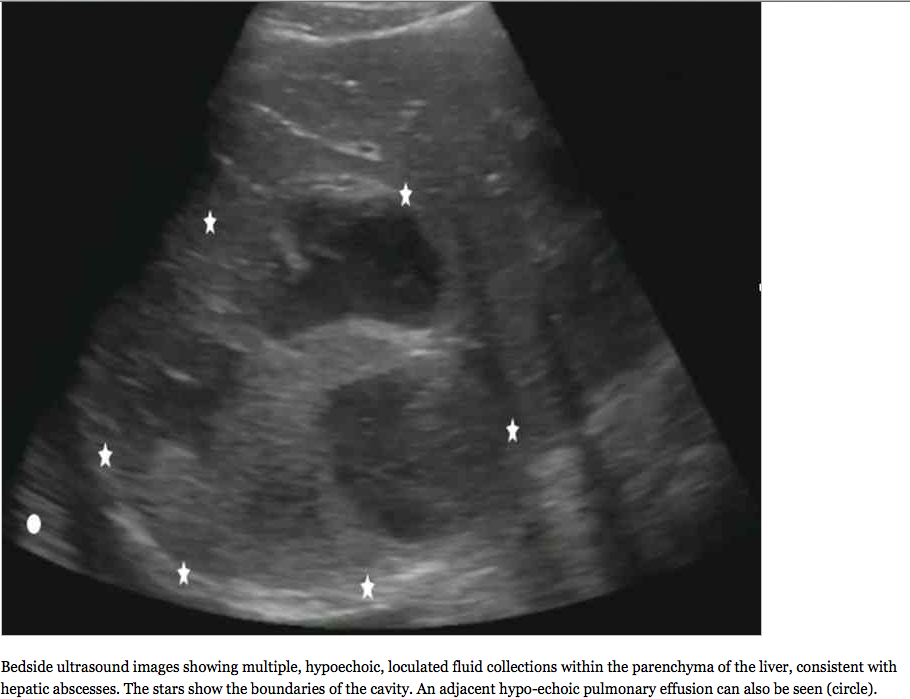

The initial diagnostic test ordered was a chest radiograph, which showed 80% opacification of the right hemithorax, consistent with pneumonia and associated parapneumonic effusion seen in Figure 1. A bedside ultrasound was subsequently performed in the ED, initially in order to examine the size of the pleural effusion in which a startling discovery was made…..”

So, “what is that?” – you may be asking…. and what happened to the patient, what can be done about it, and what is the evidence based review on the topic? Read on as Dr. McKaigney does an excellent job in discussing it all….here